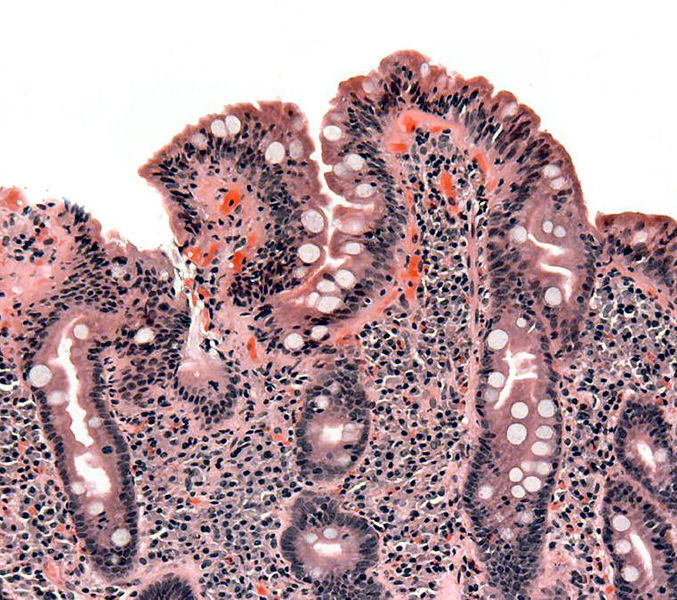

- How severely their intestines have been damaged